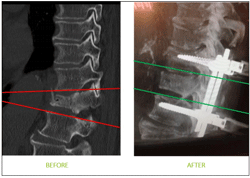

Auto-Adjust est un nouveau système breveté de vis très innovant permettant désormais à Safe Orthopaedics d’adresser le segment de la traumatologie du rachis, estimé à 800 M€ dans le monde. Cet implant permet une réduction simplifiée et optimale des fractures vertébrales.

La vis Auto-Adjust se présente comme une vis multi-axiale facilitant le placement des tiges de liaison mais qui fonctionne comme une vis à tête fixe afin de permettre le redressement des vertèbres. Le système réduit progressivement et automatiquement la fracture dans un geste identique à celui pratiqué lors d’une chirurgie traditionnelle de fusion vertébrale.

Dr Jasper Wolfs, neurochirurgien au Centre Médical de Leidschendam (Pays-Bas), ajoute : « La vis Auto-Adjust combine les avantages d’une vis polyaxiale et d’une vis monoaxiale. Elle est la seule capable de réaligner les vertèbres pour restaurer l’équilibre sagittal. Nous étions en attente d’un tel implant. »